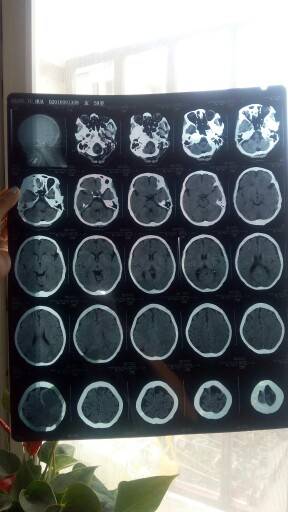

我妈肺腺癌脑转,服用

特罗凯

五个月,今天复查结果,大夫也没说啥,就说骨密度低下。是什么情况?吃啥补啥吗?